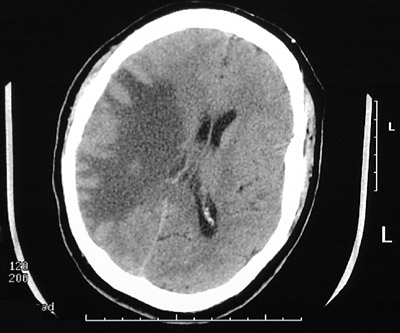

| The CT scan views of the head above and below demonstrate areas of low attenuation representing marked vasogenic edema adjacent to an area of tuberculous meningitis and tuberculoma formation in a patient with disseminated tuberculosis. Note the effacement of the lateral ventricles on the left and the shift of the midline. |